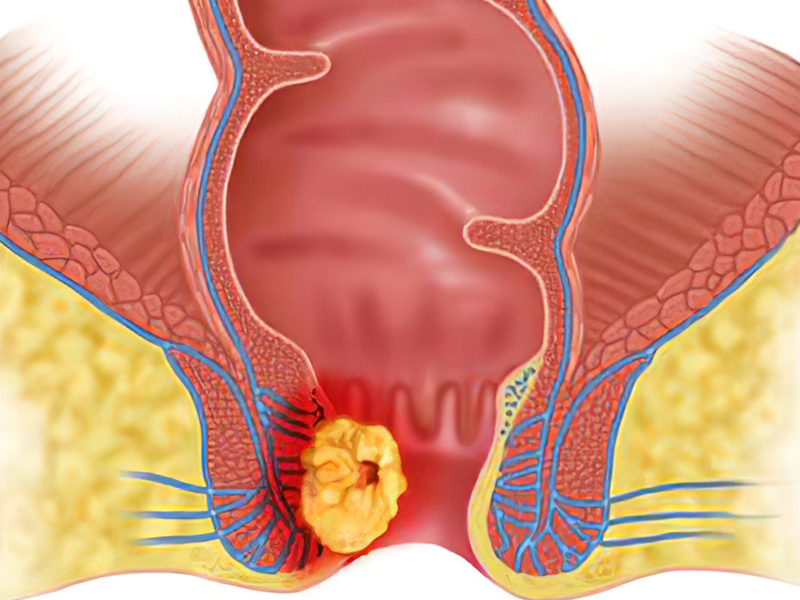

| 尿液中出现泡沫有时只是普通的生理反应,但在特定情况下,可能预示更严重的健康问题。尿液中的泡沫通常会在 10 至 20 秒内自然消失,可能因平时水分摄取不够,身体呈现局部脱水现象,尿液变得浓稠易产生泡沫。 或者是大鱼大肉摄取过多的蛋白质,尿液中可能会暂时出现蛋白质排出,导致泡沫增多,又可能是在运动过后,因运动会加速血液循环,也有可能导致尿液中暂时出现泡沫,大多数情况下都是无害的现象,这些情况下的泡沫通常会在短时间内自行消失,不需要特别治疗。 若有泡沫持续很久都不消失,或者伴随尿液颜色改变、排尿困难等其他症状,这就有可能是身体发出健康警讯,如肾脏功能受损,肾脏疾病可能引起肾脏无法回收蛋白质,导致尿蛋白过量,从而产生泡泡尿,或是糖尿病,糖尿病患者的尿液中含有过量的糖分,导致泡沫产生。 另还有可能是泌尿道感染,尿道感染可能导致尿液中出现异常物质,形成泡沫,亦或是摄护腺肥大,男性若有摄护腺肥大问题可能影响尿液流动,导致泡沫产生,有上述这些状况时建议就医进行尿液检查,以确定是否有健康问题,并进行适当的治疗。 一般来说,发现尿液中的泡沫不需要太恐慌,但如果有持续的泡沫或其他症状,则应进行进一步的身体检查,只要保持健康的生活方式,均衡饮食、适量运动和充足的水分摄取,就是维持排尿健康的关键。 |